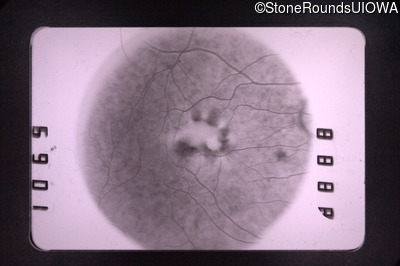

Visit at age: 47 years

Fluorescein Angiography - Right - 20/70